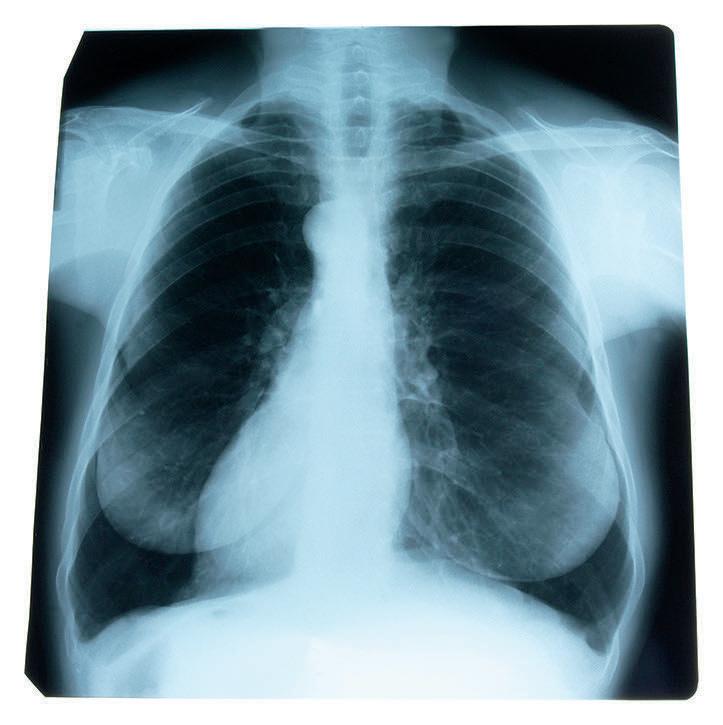

Common respiratory ailments

Oxygen is essential to life. The respiratory system works tirelessly to provide fresh oxygen to the body and ensure that all metabolic activities can occur unhindered. The respiratory system is what makes the inhalation and exhalation of air possible, and it’s responsible for the distribution of oxygen throughout the body. The respiratory system is a network of organs and tissues that help a person breathe. In addition to facilitating the absorption of oxygen from the air, the respiratory system cleans out waste gases like carbon dioxide. In a healthy person, the respiratory system functions like a well-oiled machine. But that same system is sometimes hampered by illness, allergies and infections, according to the Cleveland Clinic. With so much riding on a healthy respiratory system, it can help to learn about some of the more common conditions that can affect it.

•Asthma: Asthma is a chronic inflammatory disease caused by narrowed airways affected by inflammation. Asthma causes breathing difficulties, coughing, wheezing, and other symptoms. Most people need to take preventive medicines to control symptoms.

•COPD: Chronic obstructive pulmonary disease is comprised of chronic bronchitis and emphysema. Bronchitis is when the lining of the bronchial tubes becomes inflamed and irritated. Swelling may cause an abundance of mucus. Emphysema occurs when the tiny air sacs (alveoli) become damaged and less flexible. This reduces the alveoli’s ability to move oxygen and other gases, which adversely affects breathing, according to Verywell Health.

•Influenza: Influenza, also known as the flu, is a viral illness that can produce a number of symptoms. The flu viruses can be inhaled or brought into the body by touching items that contain the virus. Mild fever, runny

nose, cough, fatigue, and sore throat are common symptoms of influenza. While most people recover, the Mayo Clinic warns that flu complications can be deadly.

•COVID-19: SARS-CoV-2 is the virus responsible for causing COVID-19, which was discovered in the winter of 2019. It is a highly infectious illness caused by a coronavirus. It is spread from person to person, and has caused millions of deaths around the world as well as lasting health problems, according to Johns Hopkins Medicine. Depending on the individual, the effects of COVID-19 can be mild or severe. Because the virus mutates easily, researchers continue to develop new vaccines to help boost defense against it. Symptoms appear within two to 14 days of exposure to the virus. A person infected with the coronavirus is contagious to others for up to two days before symptoms appear, and they remain contagious to others for 10 to 20 days, depending on their immune system and the severity of their illness.

•Tuberculosis: TB is a contagious and potentially life-threatening infectious disease caused by the bacterium mycobacterium tuberculosis, which is spread through the air. The CDC says TB is preventable and treatable in most cases. Infection control practices can help reduce TB transmission.

•Pneumonia: With pneumonia, a virus, bacteria or another infectious agent causes alveoli to fill with fluid or pus, affecting breathing and gas exchange. Pneumonia symptoms may be mild and not affect daily activities, while others can be severe and require hospitalization.

•Cystic fibrosis: This is a genetic condition that creates very thick mucus in the body, which can cause both breathing and digestive problems. Blockages from thick mucus can trap harmful bacteria and lead to infections, says the Mayo Clinic.